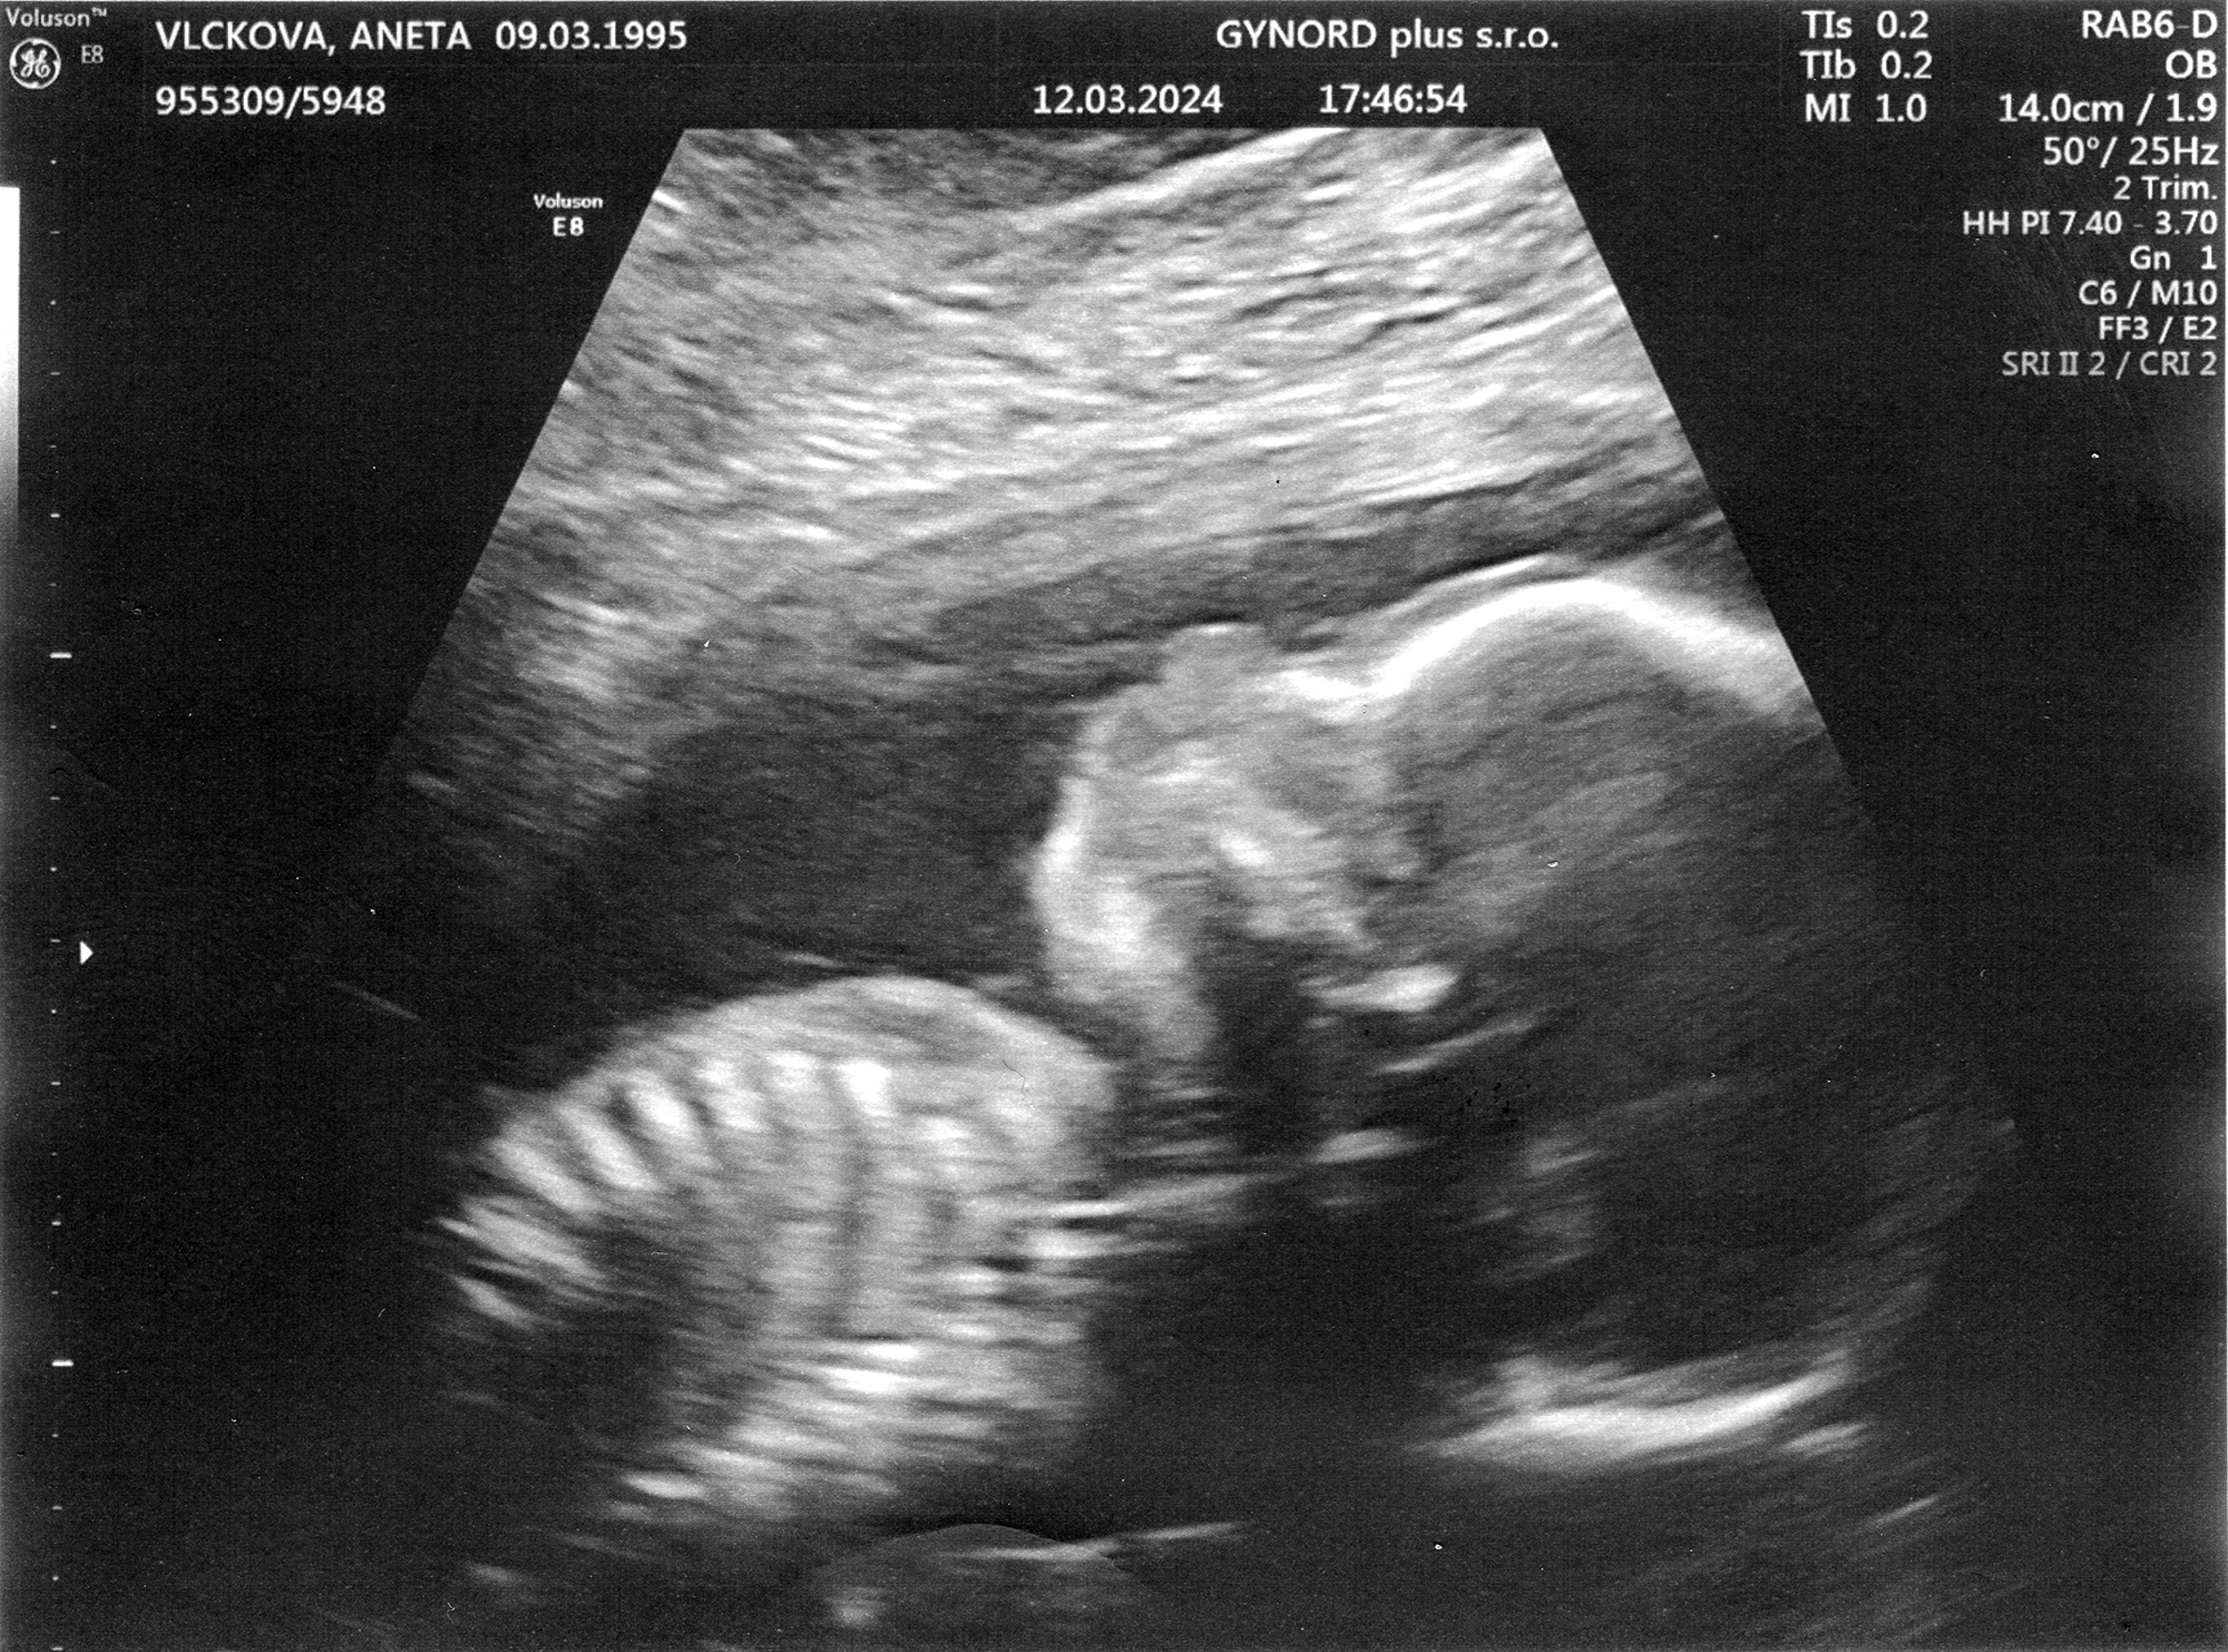

Tomášek - ještě v bříšku